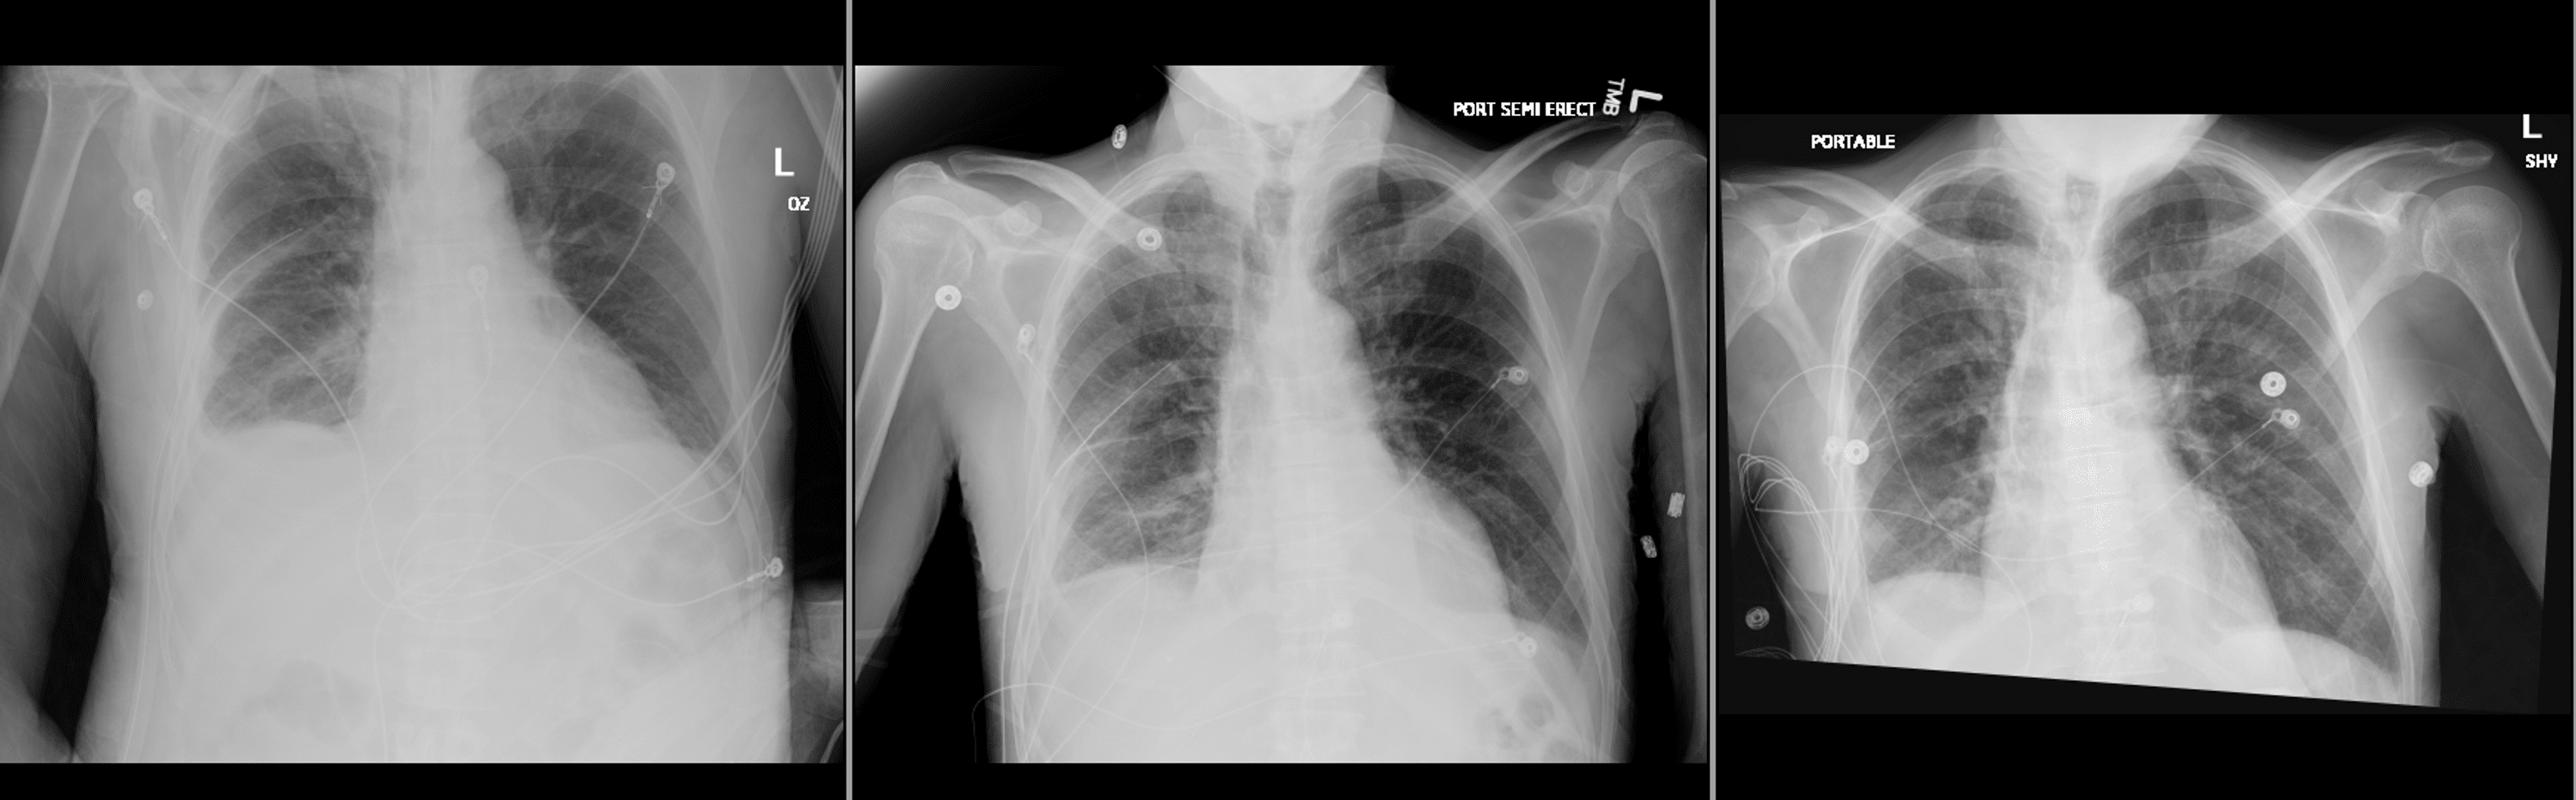

Chest Xray depicting a rightsided chest tube (red arrow), minimal How Is A Chest Tube Removed A chest tube is a plastic tube used to remove air, blood, or other fluids from a space between your lungs and chest cavity. A chest tube is a tube that is put in through the chest wall, between the ribs. General recommendations regarding the criteria and timing of chest tube removal exist; A chest tube is placed through the. How Is A Chest Tube Removed.

Chest Xray, Chest radiography demonstrating and esophageal chest tube How Is A Chest Tube Removed Chest drainage tubes, also known as thoracostomy tubes or simply “chest tubes,” are vital medical devices used to remove air, fluids,. A chest tube is placed through the chest wall between two ribs. This tube is used to drain air, fluid or both from around your lungs. When fluid or air collects in the pleural space, the lungs can’t expand. How Is A Chest Tube Removed.